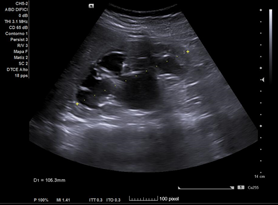

En ecografía clínica desde el centro de salud, se objetiva gran dilatación del sistema excretor del riñón derecho, con adelgazamiento de la cortical (hidronefrosis grado III-IV). No se aprecia litiasis u otra causa obstructiva a nivel renoureteral ni vesical. Riñón derecho conserva tamaño normal. Riñón izquierdo de tamaño y ecoestructura normales, sin dilatación piélica. Vejiga bien replecionada sin alteraciones en su pared.

Juicio Clínico: Riñón derecho con dilatación de su sistema excretor.

Concordancia con el hospital. Se realiza Urografía por Tomografía Computada que confirma hidronefrosis grado IV en riñón derecho; no se objetivan litiasis renoureterales; se aprecia arteria accesoria polar inferior de dicho riñón, la cual cruza la unión pieloureteral ipsilateral.